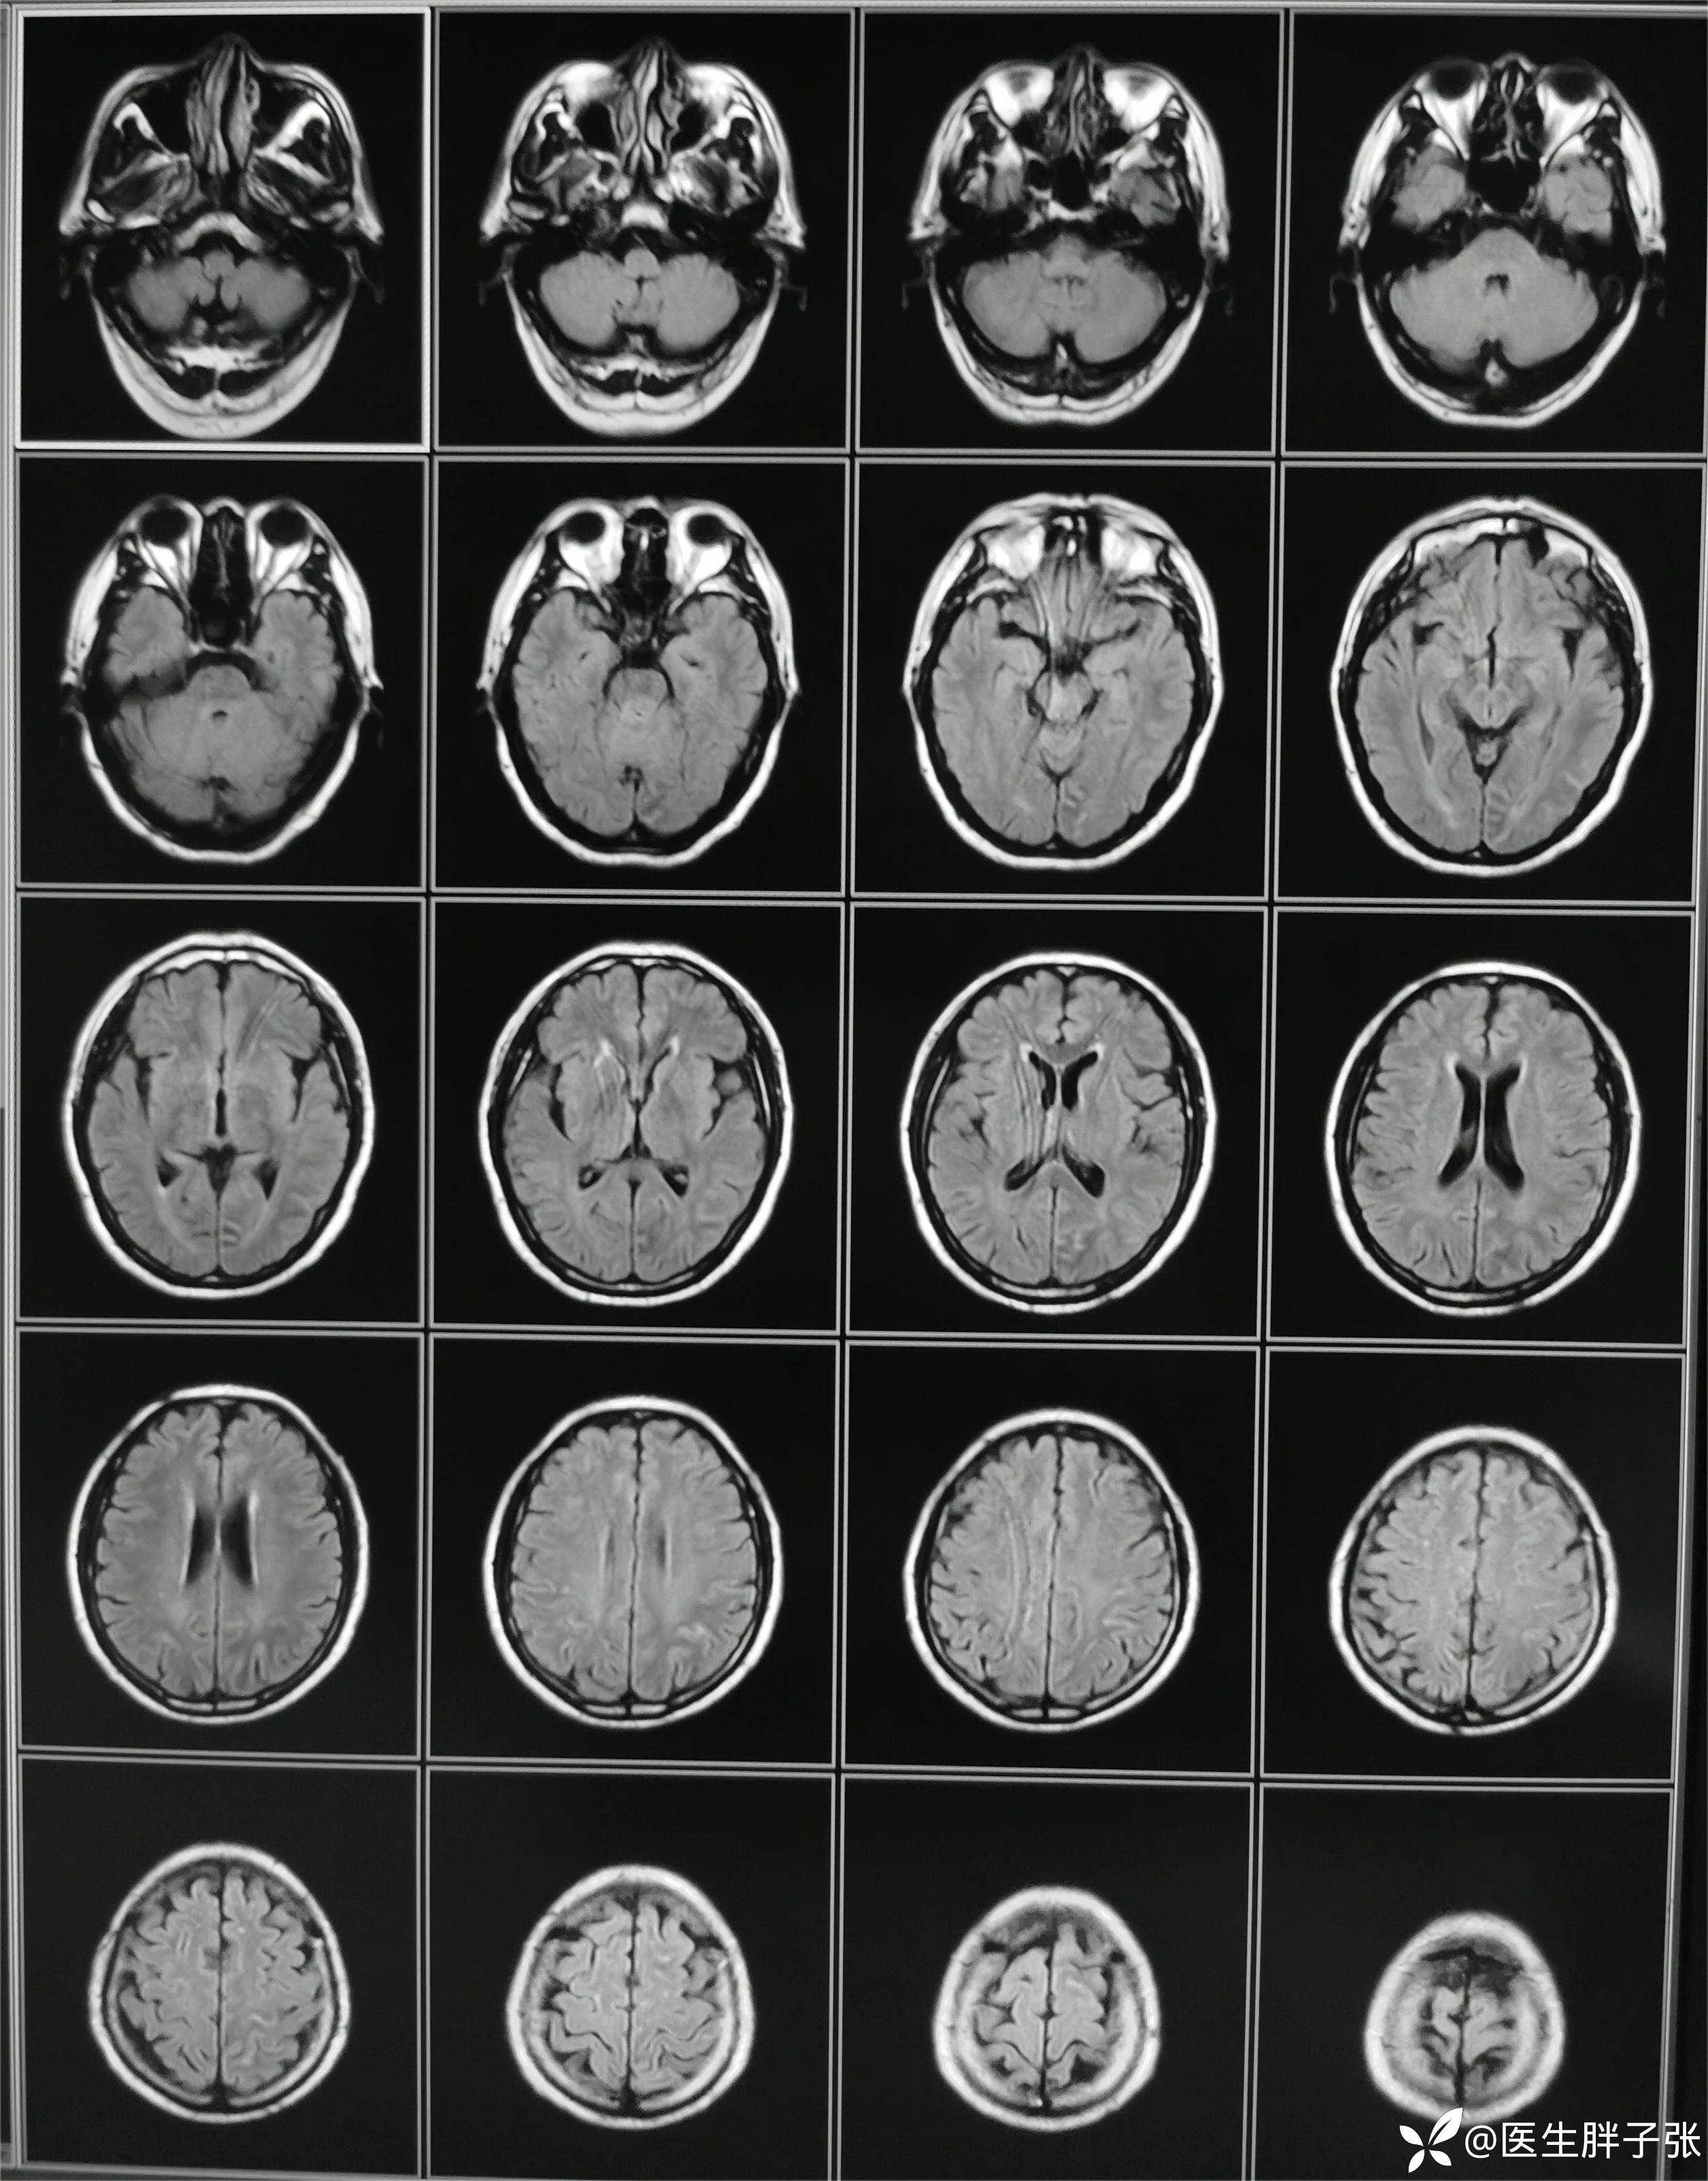

颅脑MR回报左侧顶叶新近梗死灶;多发腔隙性脑梗死及缺血灶;MRA未见异常。

再次查看核磁,考虑患者左侧顶枕叶及右侧枕叶脑组织存在混杂信号。

查房意见:颅脑MR存在顶叶新近梗死,椎动脉作为责任血管的梗死可能性大。患者存在前驱感染,需除外颅内感染、自免脑、副肿瘤可能。